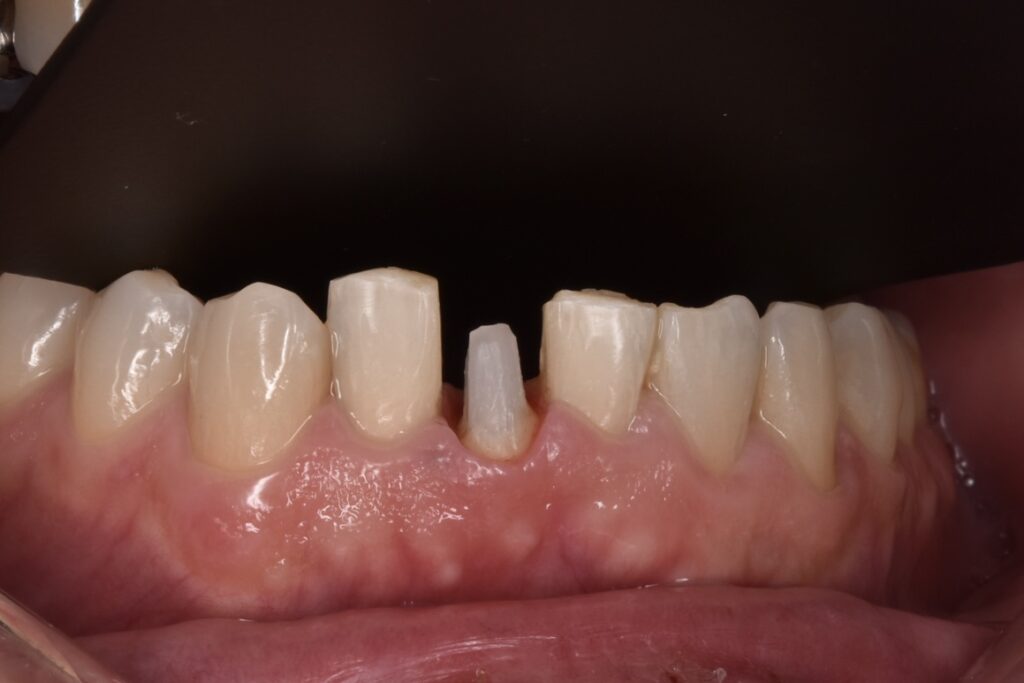

歯が折れてしまっている現状では、このままセラミックをやりかえても予後が悪く長持ちしない点をお伝えしました。そこでご自身の歯を上に引っ張り出して骨からの距離を出してからセラミックで修復する意図的挺出(いとてきていしゅつ)をご提案させて頂きました。

完成したセラミック

さくらジルコニアプランでのジルコニアセラミックです。歯の色はA3というシェードです。色見本が20色近くありますので、そちらから選択して頂きます。